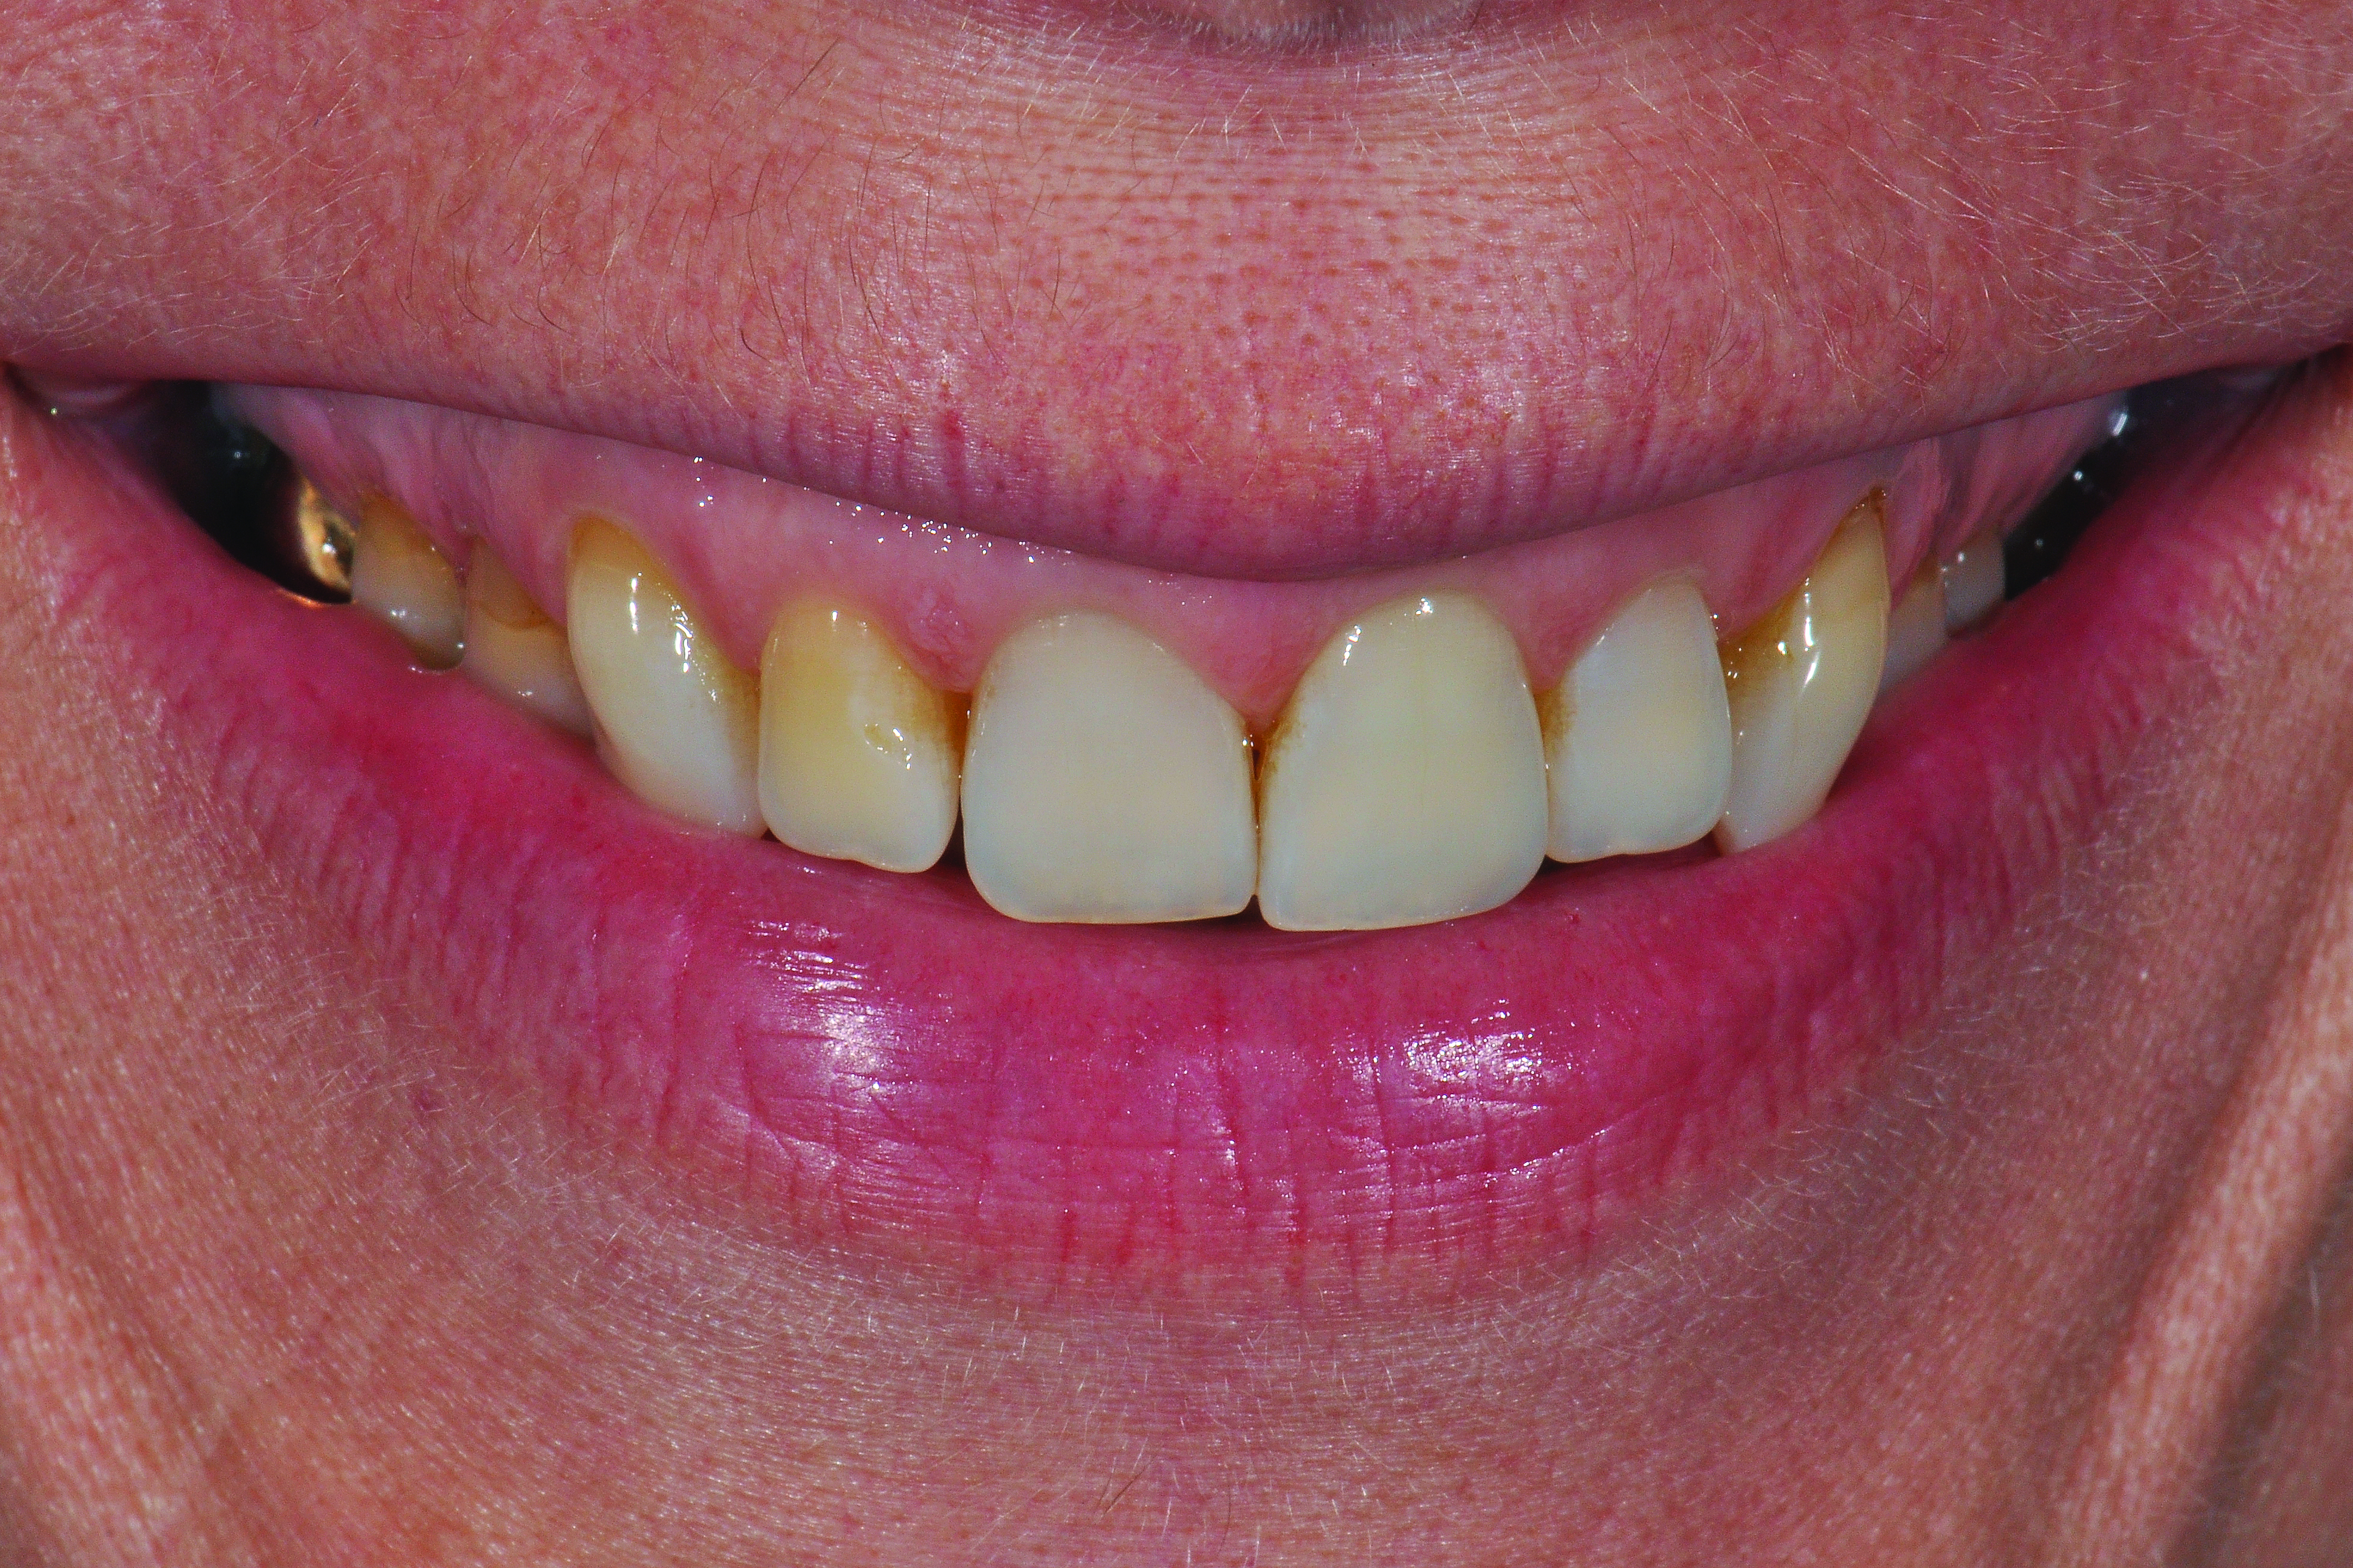

After consultation with the patient regarding these findings, an implant strategy was chosen. The patient was made aware of several esthetic challenges related to her case, including a high smile line (Figure 4), ankylosis of the tooth to be extracted, and long-term maintenance of the alveolar process and associated mucosal topography post-extraction due to a very thin facial cortex of bone labial to tooth No. 8.

Fig 2. Frontal pre-operative view demonstrating acceptable mucosal esthetics.

Figure 2

Fig 4. The patient demonstrates a high smile line, leading to a much higher esthetic risk factor during treatment planning for implant therapy.

Figure 4